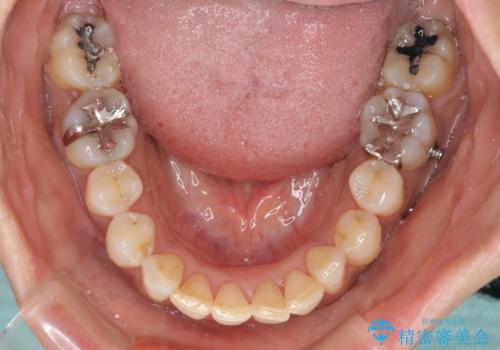

なかなか装着時間が守れず、後戻りを繰り返しながら治療を進めたため、インビザライン治療期間期限ギリギリの5年弱の期間を要しました。

- マウスピース型矯正装置の長時間装着(1日20時間以上)が必須です

- 治療計画通りに進めるためには、患者様の意志が重要になります